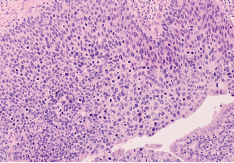

De infectiecyclus van HPV is uitsluitend intra-epitheliaal en infecteert zowel het cutane als het mucosale plaveiselepitheel.

Cervicale intra-epitheliale neoplasie (CIN) is een voorstadium van kanker waarbij abnormale cellen aan de oppervlakte van de baarmoederhals groeien.4 Dit is een van de kankersoorten die HPV gerelateerd kunnen zijn.

CIN kan worden ingedeeld op basis van de mate waarin het epitheelweefsel is aangetast:

• CIN 1 (laaggradige neoplasie) verwijst naar een dysplasie die ongeveer één derde van de dikte van het epitheel betreft.

• CIN 2 verwijst naar abnormale veranderingen in ongeveer één tot twee derde van de epitheel laag.

• CIN 3 beschrijft een aandoening waarbij meer dan twee-derde van het epitheel is aangetast.5

De infectiecyclus van HPV is uitsluitend intra-epitheliaal en infecteert zowel het cutane als het mucosale plaveiselepitheel.8